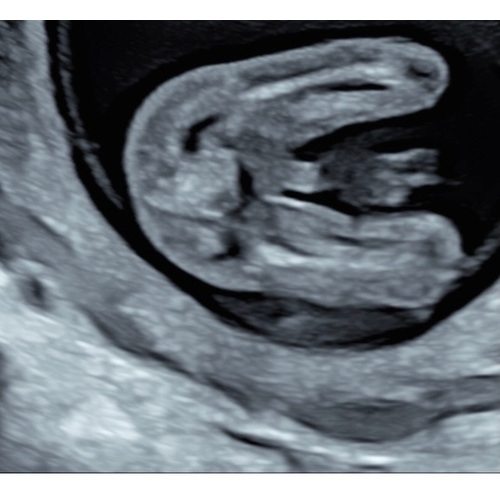

Dit was bij ons met 14 weken:)

Met 15 weken 💙